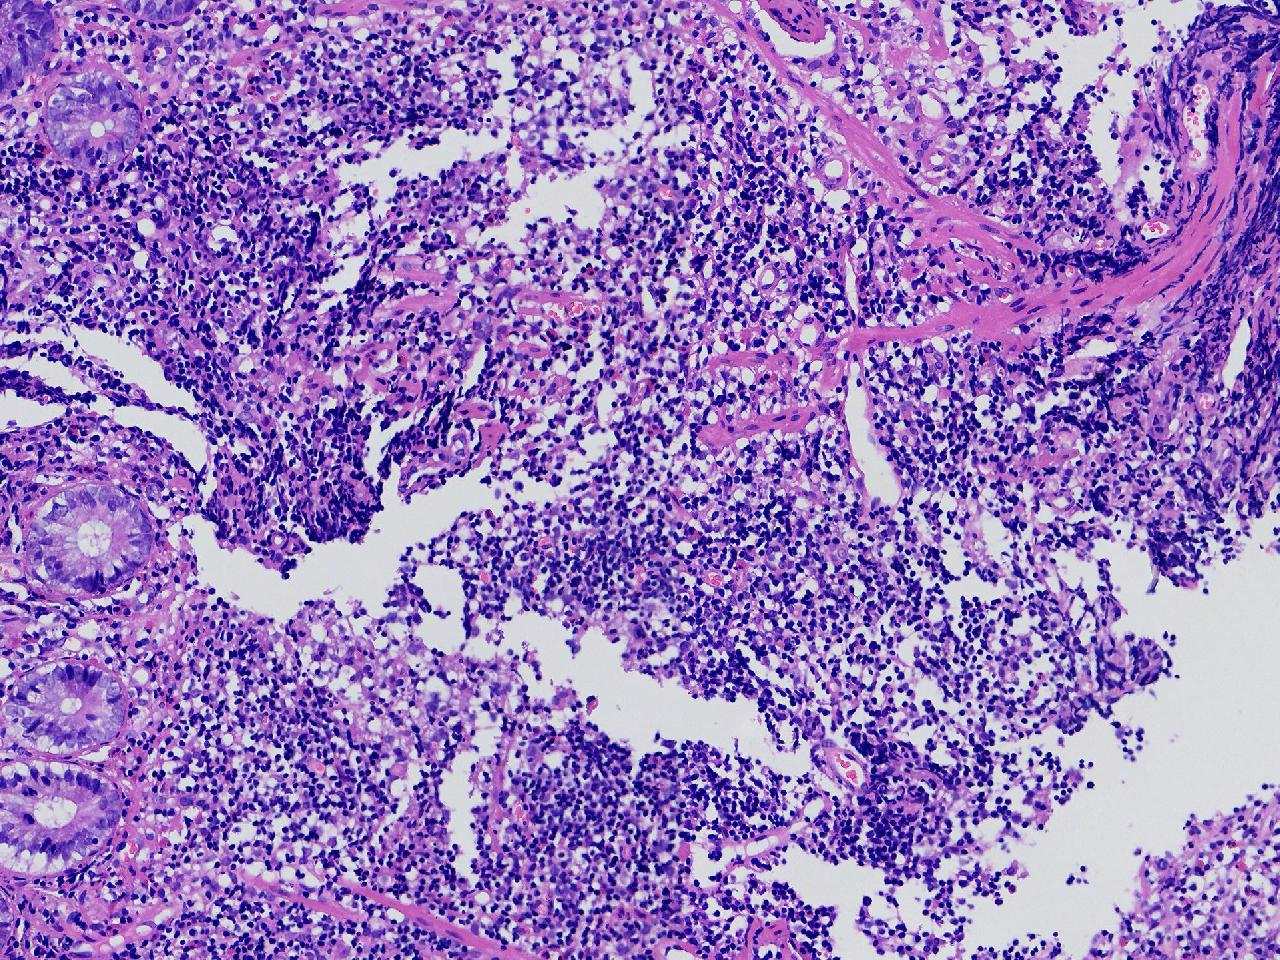

男,62岁,回盲部附近见多发片状溃疡,底覆薄白苔,周围粘膜充血水肿,活检2块,质软,弹性可。

回盲部活检

灰白色不整形软组织2块,直径均0.2厘米。

考虑:溃疡性结肠炎?

炎症性肠病要考虑,具体的类型不太好确定,需要结合临床。

上级医院会诊,不除外炎症性肠病,结合临床。